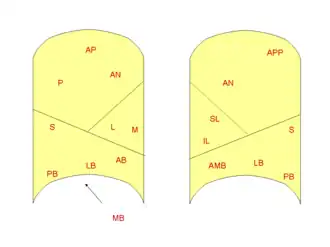

Right lung

- Superior lobe

- apical segment

- posterior segment

- anterior segment

- Middle lobe

- lateral segment

- medial segment

- Inferior lobe

- superior segment

- medial-basal segment

- anterior-basal segment

- lateral-basal segment

- posterior-basal segment

Left lung

- Superior lobe

- apico-posterior segment (merger of "apical" and "posterior")

- anterior segment

- Lingula of superior lobe

- inferior lingular segment

- superior lingular segment

- Inferior lobe

- superior segment

- anteromedial basal segment (merger of "anterior basal" and "medial basal")

- posterior basal segment

- lateral basal segment